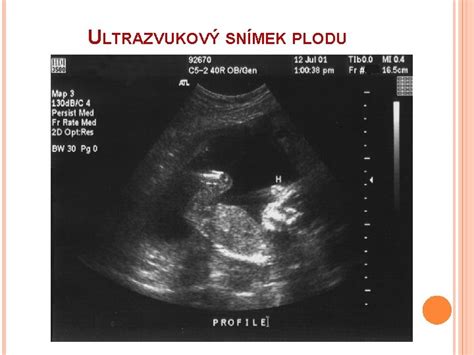

Každá kapitola takejto knihy je navrhnutá tak, aby poskytla cenné informácie pre konkrétny týždeň tehotenstva. Nájdete tu odporúčania, na čo nezabudnúť, na čo si dávať pozor, aby sa predišlo komplikáciám, ako sa mení telo matky, a samozrejme, podrobné údaje o bábätku, vrátane ultrazvukových obrázkov. Tieto sprievodcovia často zahŕňajú aj rady týkajúce sa tehotenskej módy, výberu bezpečných produktov pre deti a tipy, ako si udržať atraktivitu počas tehotenstva.